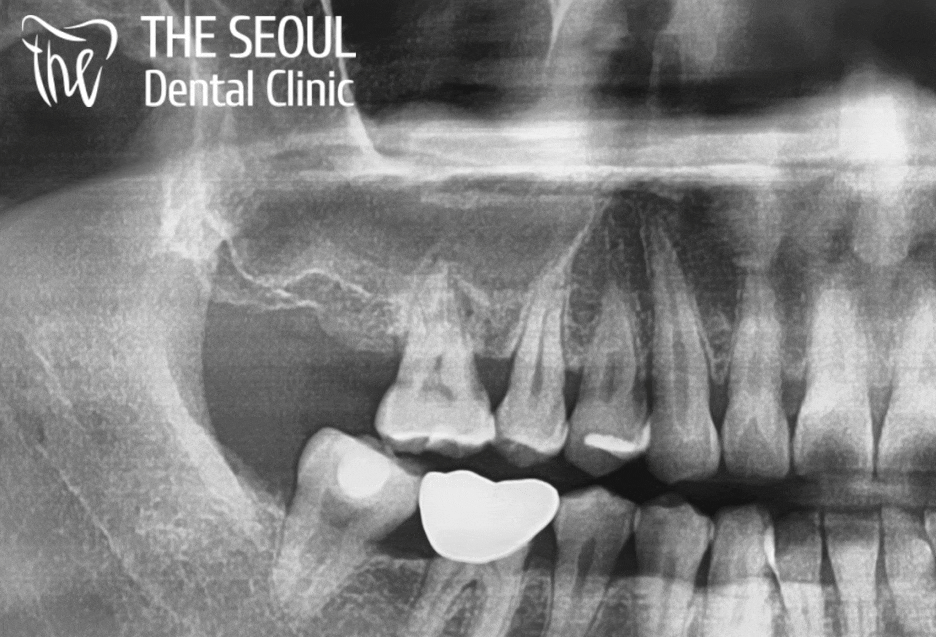

통증을 느끼셨던 곳을 살펴보니,

심한 충치와 염증이 나타났으며

그로 인해 치조골 소실이 일어나

제대로 된 고정력을 받지 못하고 있었습니다.

음.. 그로 인해 통증을 심하게 느끼셨을 것 같은데요.

아무래도 더는 살릴 수 없을 거란 판단이 들었습니다.

법랑질, 상아질에만 퍼졌다면

충치치료를 진행하여 해결할 수 있지만

이미 병소 자체가 치수를 넘어 치조골까지

괴롭히고 있었던 상황이었습니다.